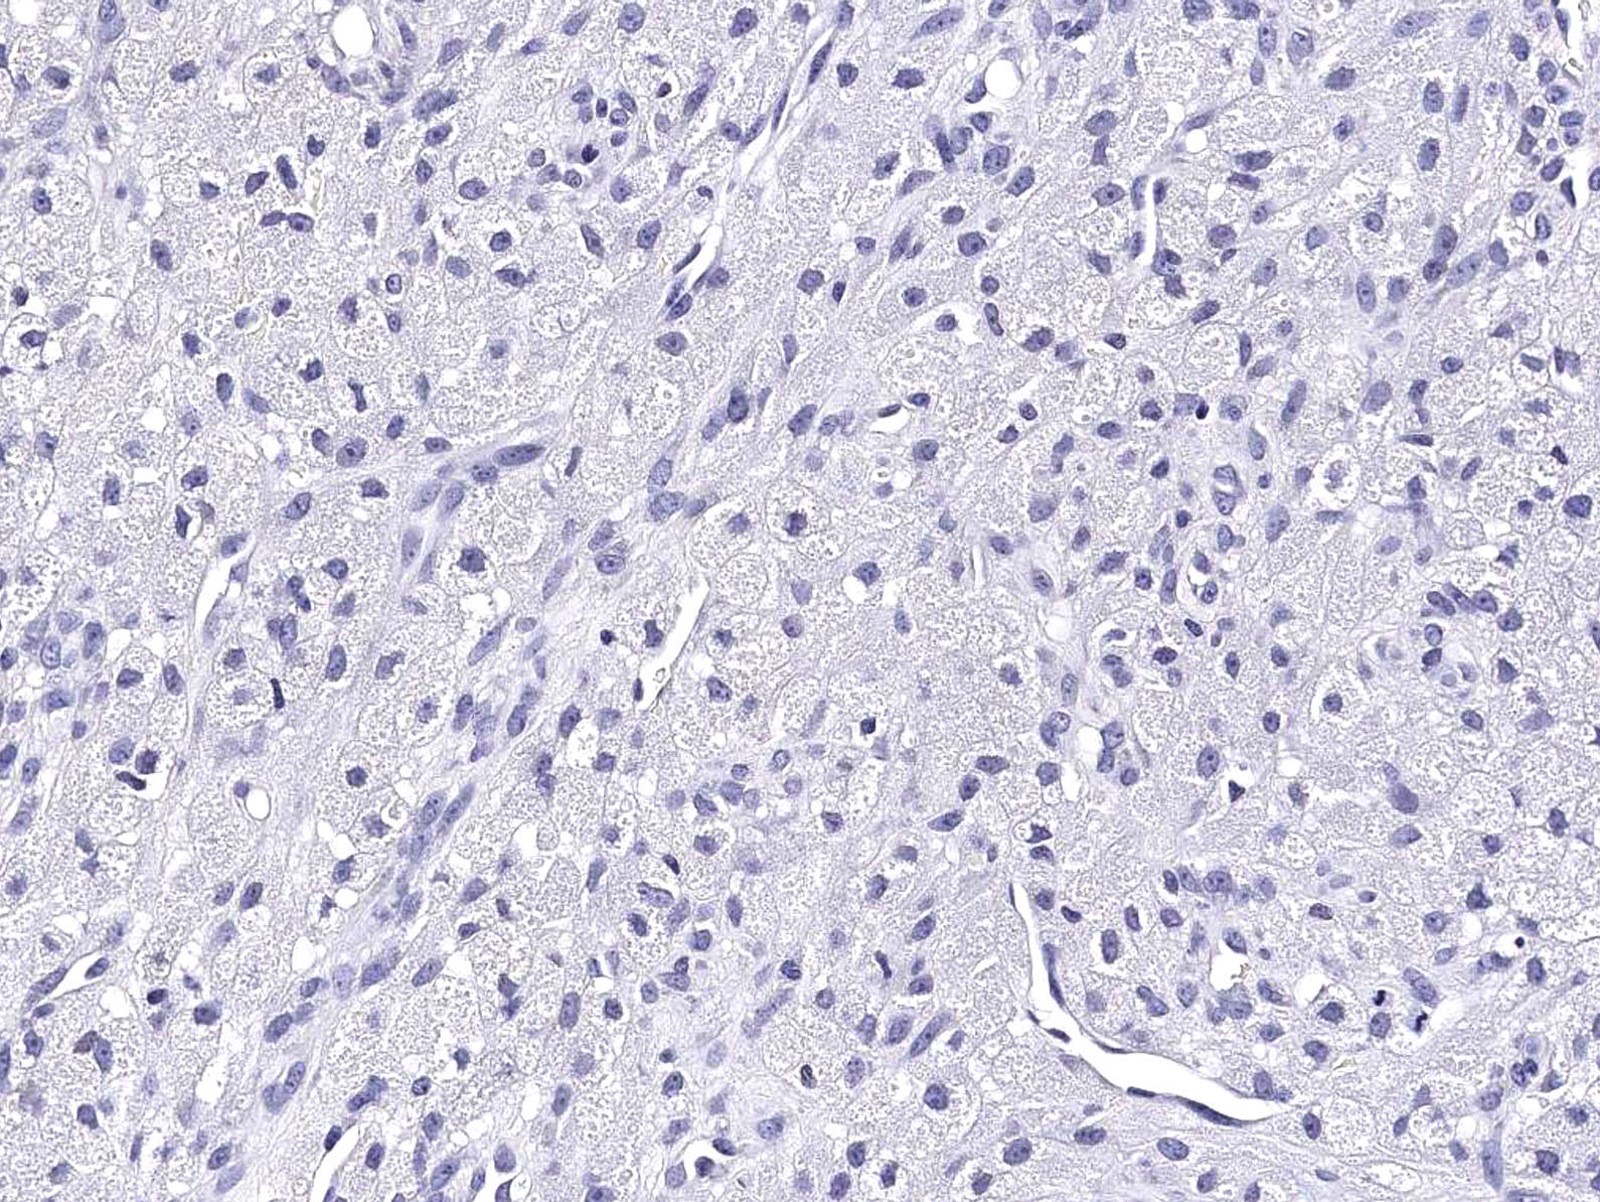

Microscopic (histologic) images

Contributed by Jarish Cohen, M.D., Ph.D.

Negative stains

- HMB45, MelanA, AE1 / AE3, EMA, desmin

- Nonneural granular cell tumor is negative for S100

- References: Am J Dermatopathol 2007;29:22, Am J Surg Pathol 1991;15:48